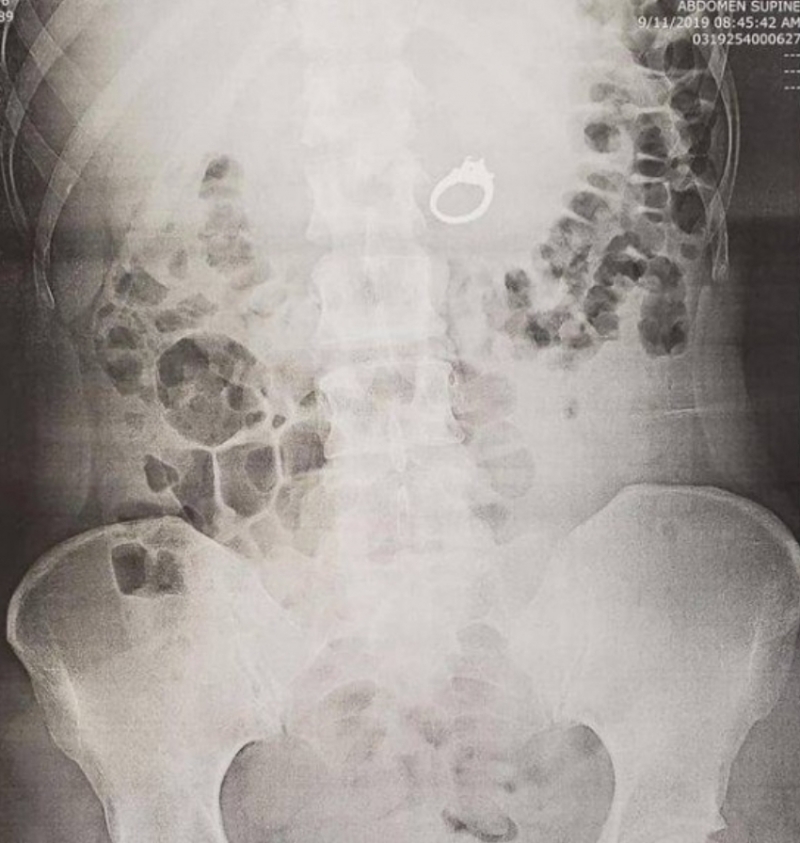

والشابة التي تدعى جينا، وتبلغ من العمر 29 عاما، ابتلعت خاتم خطبتها أثناء نومها،

بعد أن حلمت بأنها كانت على متن قطار وتحاول الهروب من إحدى العصابات التي أرادت سرقة الخاتم، لتقوم بخلعه وابتلاعه لحمايته من السرقة.

ولم تدرك جينا أنها ابتلعت خاتم خطوبتها وهي نصف نائمة، إلا عندما استيقظت في صباح اليوم التالي.

وأوضحت جينا أن الطبيب أمر بإجراء الأشعة السينية وبدأت تشعر بالصدمة إلى حد ما عندما عادت إلى الطبيب، واكتشفت أن الأشعة تظهر مكان وجود الخاتم بأمعائها.